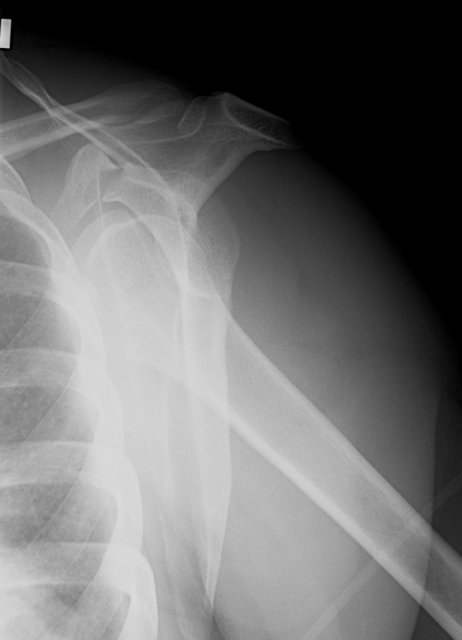

Return to Coracoid Fracture